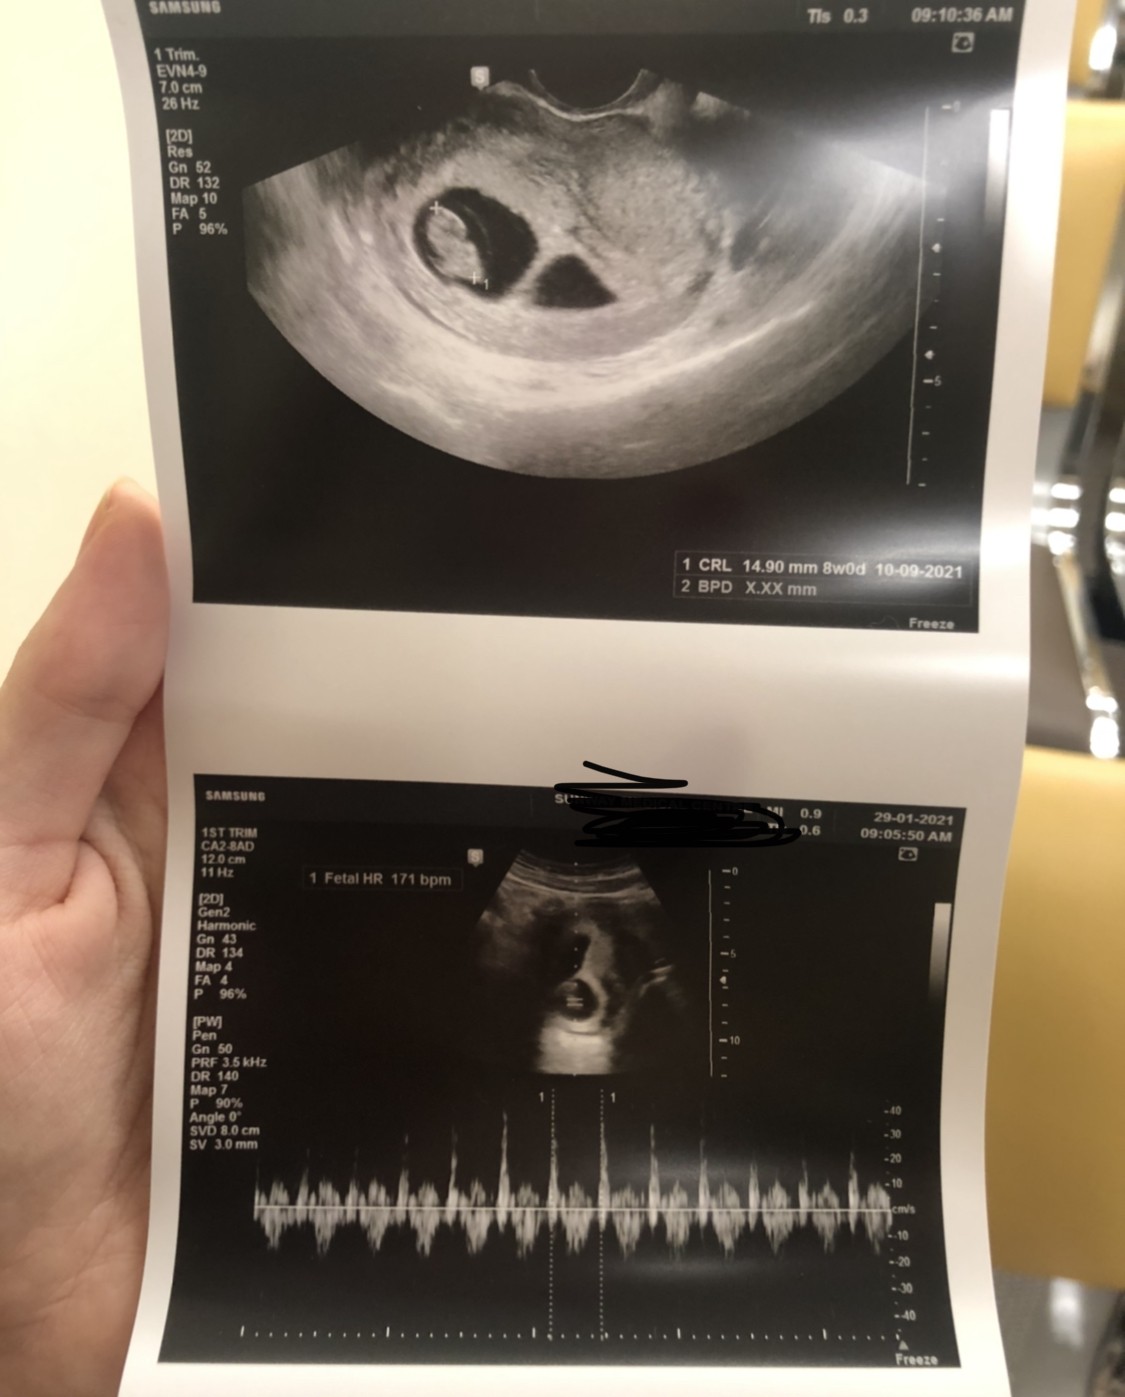

Jednak będzie jedynak! ;) ale mam drugie jajko, które jest puste, wiec oby znikło, bo mogę plamić czy krwawić :(

Poza tym usłyszałam serduszko, wszystko się zgadza, prawdopodobny termin 9/10.09❤️

wszystko jak na załączonym zdjęciu :)

Wiec mamy 8 tydzień! Następna wizyta za trzy tygodnie 😅